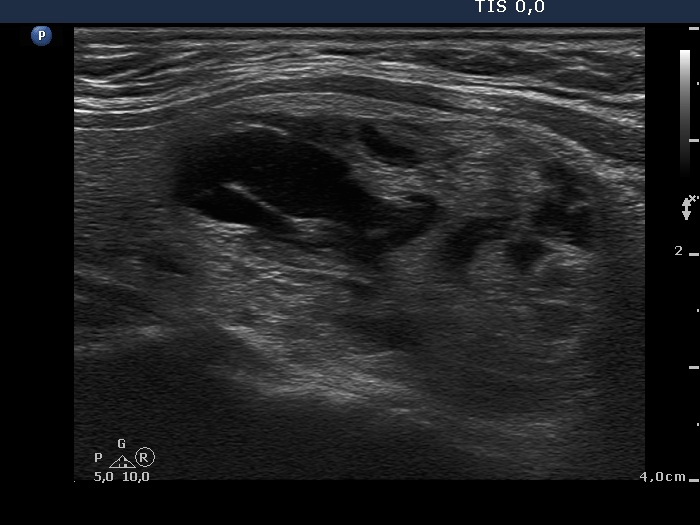

Ultrasonography: the thyroid was echonormal. There were two mixed nodules in the thyroid, one larger in the right and another smaller one in the left lobe. The vascular type of the nodules were not specific, they did not presented a halo.

After aspirating 7 mL brown fluid from the right nodule, the lesion presented a type 2 vascular pattern.